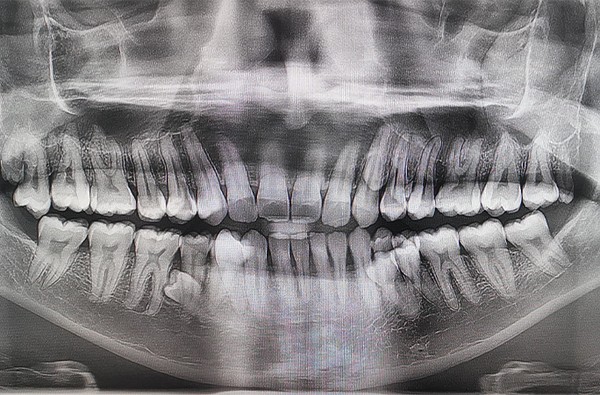

Convencido de que teria apenas três pares a mais que uma dentição normal, Prathab Muniandy chamou a atenção de especialistas por apresentar uma característica nada convencional. De acordo com exames efetuados, o homem possui 10 dentes a mais que uma pessoa adulta. No raio-X, foi mostrado que outros quatro dentes ainda não erupcionaram (que não romperam a gengiva).

Diante do cenário atípico, o malaio foi registrado no Guinness Book como o homem com mais dentes no mundo. O status somente foi possível após diversos dentistas decretarem a presença dos pares extras por meio de exames de imagem. Curiosamente, a presença das estruturas em excesso não atrapalha a vida de Muniandy, que afirmou que outras pessoas dificilmente notam a anomalia.